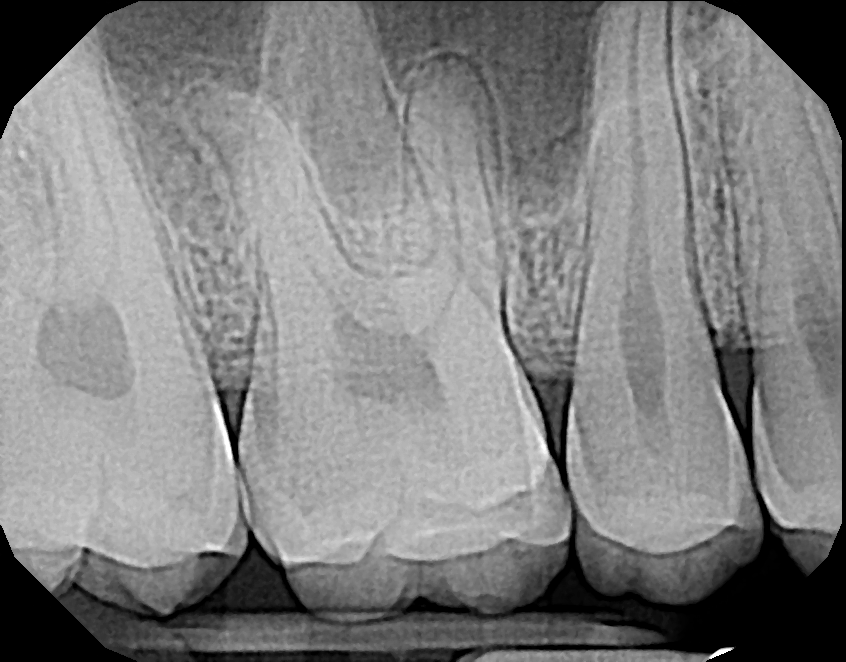

Ultimately, quality is the most important factor in a dental X-ray sensor. A sharp image ensures a proper diagnosis for patients. The Dream Sensor produces easy-to-view, crisp images that work with almost any existing dental software. The results of the direct comparison of DentiMax vs. Dexis are clear.

![]() X-ray taken with the DentiMax sensor shown in Sidexis 4™ software | ![]() X-ray taken with the Dexis™ sensor |